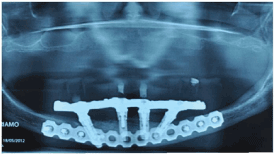

The patient underwent general anesthesia and through an extra-oral access, the mandibular fracture was reduced and affixed with a straight plate and 2.4 mm fixation screws (Synthes-Oberdorf/Switzerland), previously individualized in a prototype model (Figures 4 and 5).

Clinical controls were conducted after 15 days, when a new occlusal adjustment and check of screw torque was made.After 3, 6 and 9 months, clinical controls were conducted and after 12 months a clinical and radiograph control.In all these controls and images, clinical normalcy was observed (Figures 7 and 8).

Figure 8: Control radiograph at 12 months where a situation of normalcy can be observed in fracture treatment and around the implants.a